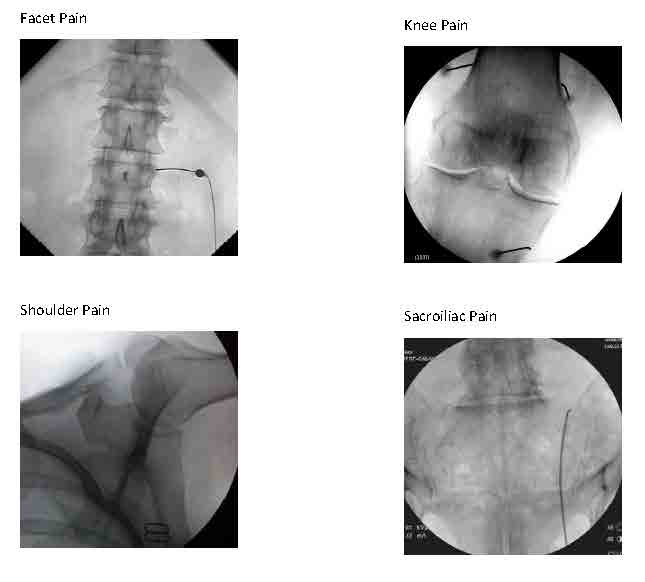

Fluoroscopic-Guided Spinal Injections

Spinal Procedures using Fluoroscopic (X-ray) Guidance

Before 1990, clinicians performed most injections “blindly,” that is, using anatomic landmarks that can be seen with the eye (observed) and felt with the hands (palpated). Such blind injections can be effective, but may miss the mark in some cases. Since 1990, our practice has been at the forefront of using image guidance to ensure the utmost precision with placement of medication with injections. Now this technologic method is standard practice.

Sacroiliac joint (SIJ) pain is a common source of lumbosacral back pain that we can diagnose and treat with 2 types of fluoroscopically guided procedures:

- Sacroiliac joint steroid injections or

- Blocks of nerves to the SIJ with local anesthetic (for diagnosis) twice to determine if blocking long term with Radiofrequency Ablation/RFA (for treatment) is recommended.

Treatment with RFA tends to last around 9 months on average (give or take 3 months), which could be 2-4 times longer than the SIJ steroid injection. However, the steroid injection requires just one session that combines diagnosis and treatment, where the RFA procedure typically requires 3-4 sessions initially. If successful, future treatments with RFA can be repeated generally without the preliminary diagnostic blocks for recurrence of the same pain.

Depiction of a left sacroiliac joint injection

We can diagnose and treat lumbar facet joint pain due to spondylosis similarly, either with a steroid injection into the joint (intra-articularly) or by blocking small nerves to these joints (medial branch blocks) with local anesthetic diagnostically and, if warranted, with RFA therapeutically (as a treatment).

We can use these same approaches to treat facet pain in the neck less frequently and in the midback rarely.

Other procedures using fluoroscopic guidance are evolving. Genicular nerve blocks that involve the usual 2 sets of diagnostic anesthetic blocks followed by blocks with RFA can be very helpful in patients with knee osteoarthritis that is either inoperable or has already failed knee joint replacement surgery. RFA nerve blocks to other joints such as the shoulder and hip for osteoarthritis are in development.